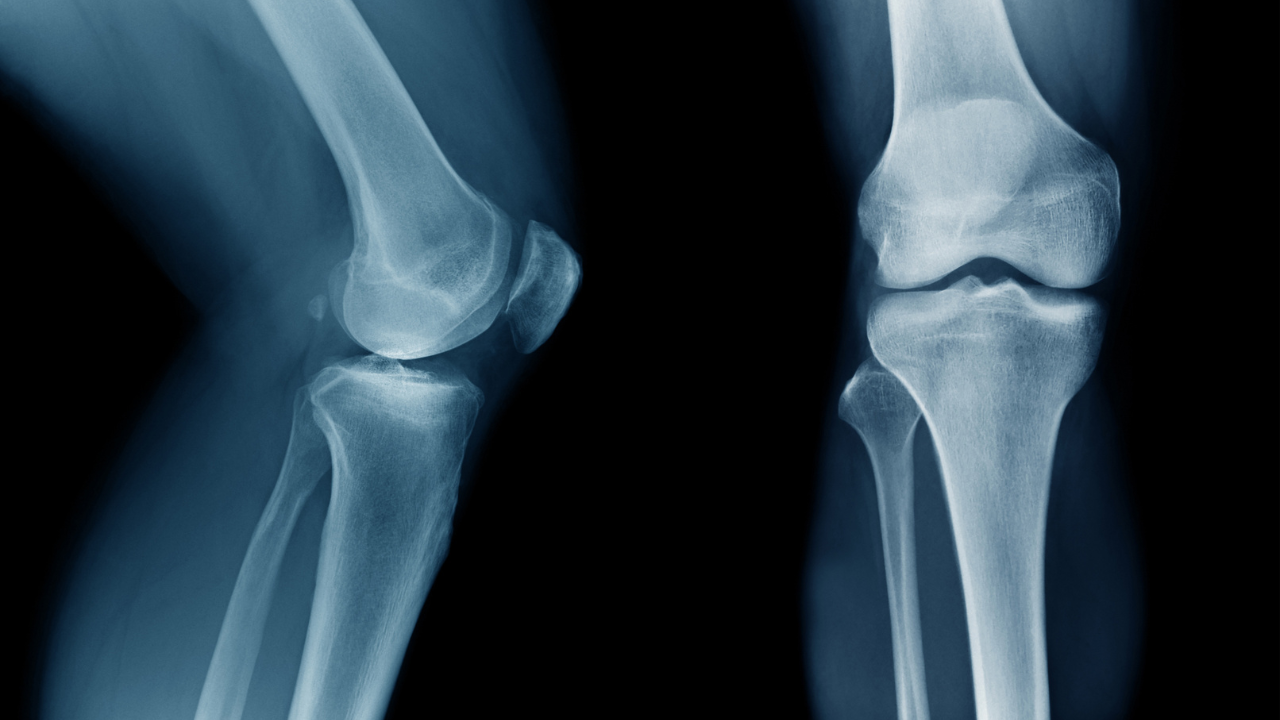

Importantly, X-ray findings do not always correlate with symptoms. Many people have clear arthritic changes on imaging but minimal discomfort. Others experience significant pain with relatively modest structural change. Pain in knee osteoarthritis is therefore not simply a measure of “how bad it looks.”

This distinction matters. Treatment decisions should be guided by symptoms and function, not imaging alone.

In many cases, a clear clinical assessment is sufficient to guide management. X-rays can confirm structural osteoarthritis but do not determine prognosis on their own. MRI scans are rarely necessary unless symptoms suggest an alternative or additional diagnosis.

Imaging can be helpful in certain circumstances, particularly when surgical decision-making is being considered. However, it should support clinical reasoning rather than replace it.Â